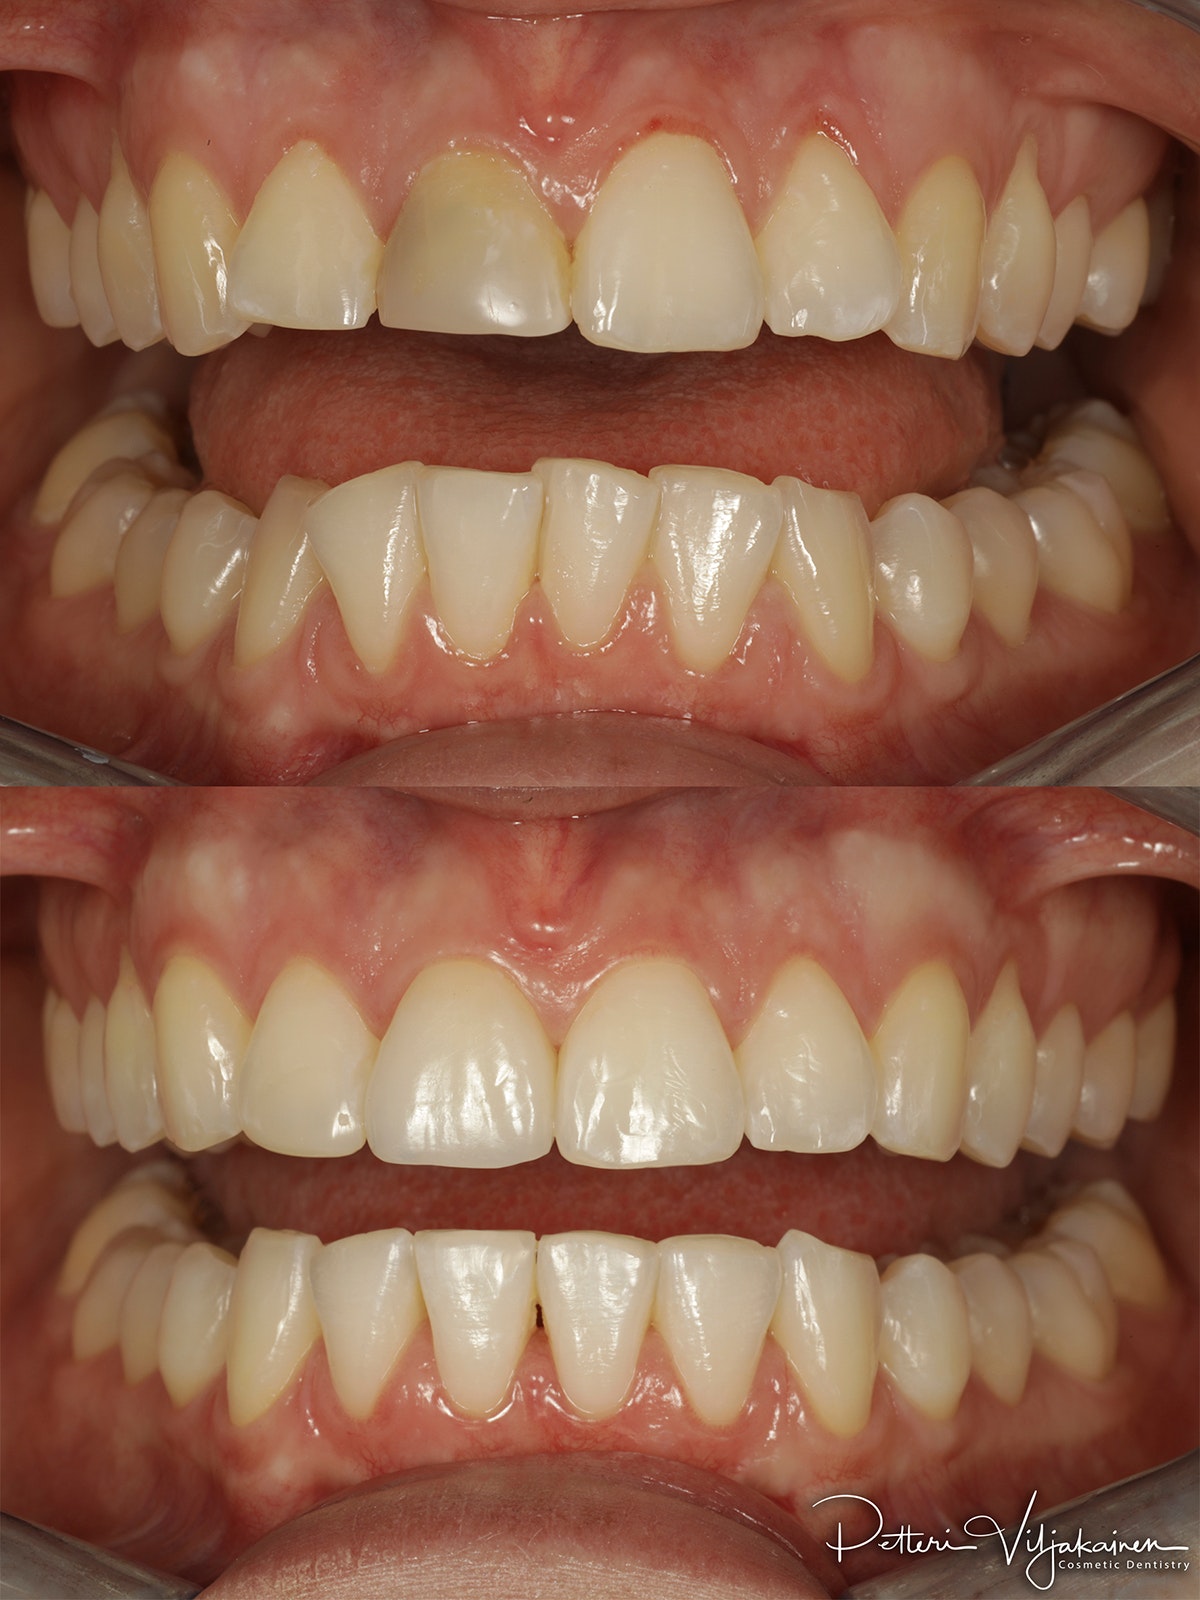

Yksittäinen laminaatti etuhampaassa

Keraamiset laminaatit reunimmaisissa yläetuhampaissa.

Oikomista tehty ennen kuoria.